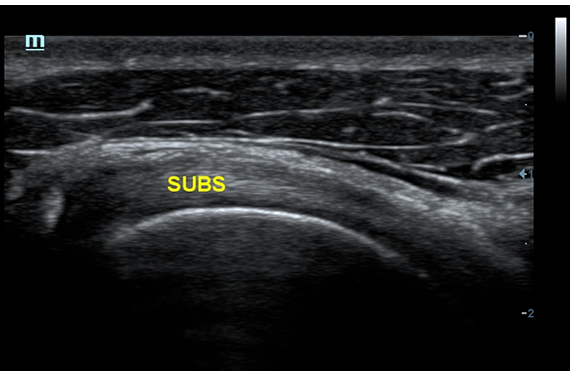

• iNeedle™ - улучшенная визуализация игл при проведении биопсии линейными датчиками

• Natural Touch Elastography - опция оценки эластичности ткани (эластография), с программой анализа. Действует на линейных датчиках 7L4A, L14-6NE и L9-3E